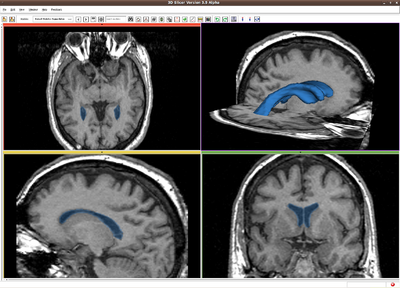

Robust Statistics Based Segmentation

RSS result for Brain MR image

Given a few initial seeds, we use the robust statistics to construct a feature image out of the original image, and the image segmentation is carried out in the feature image. To do so, we first compute the certain robust statistics, such as the median absolute deviation(MAD) and the interquartile range (IQ), from the seed points. Further, a multi-dimentional probability distribution function is computed from the feature seeds. At each point in the image, the active contour is driven by the probabilities of this pixel belonging to each category indicated by the seeds.

CLI module in 3D Slicer, in the category of Segmentation